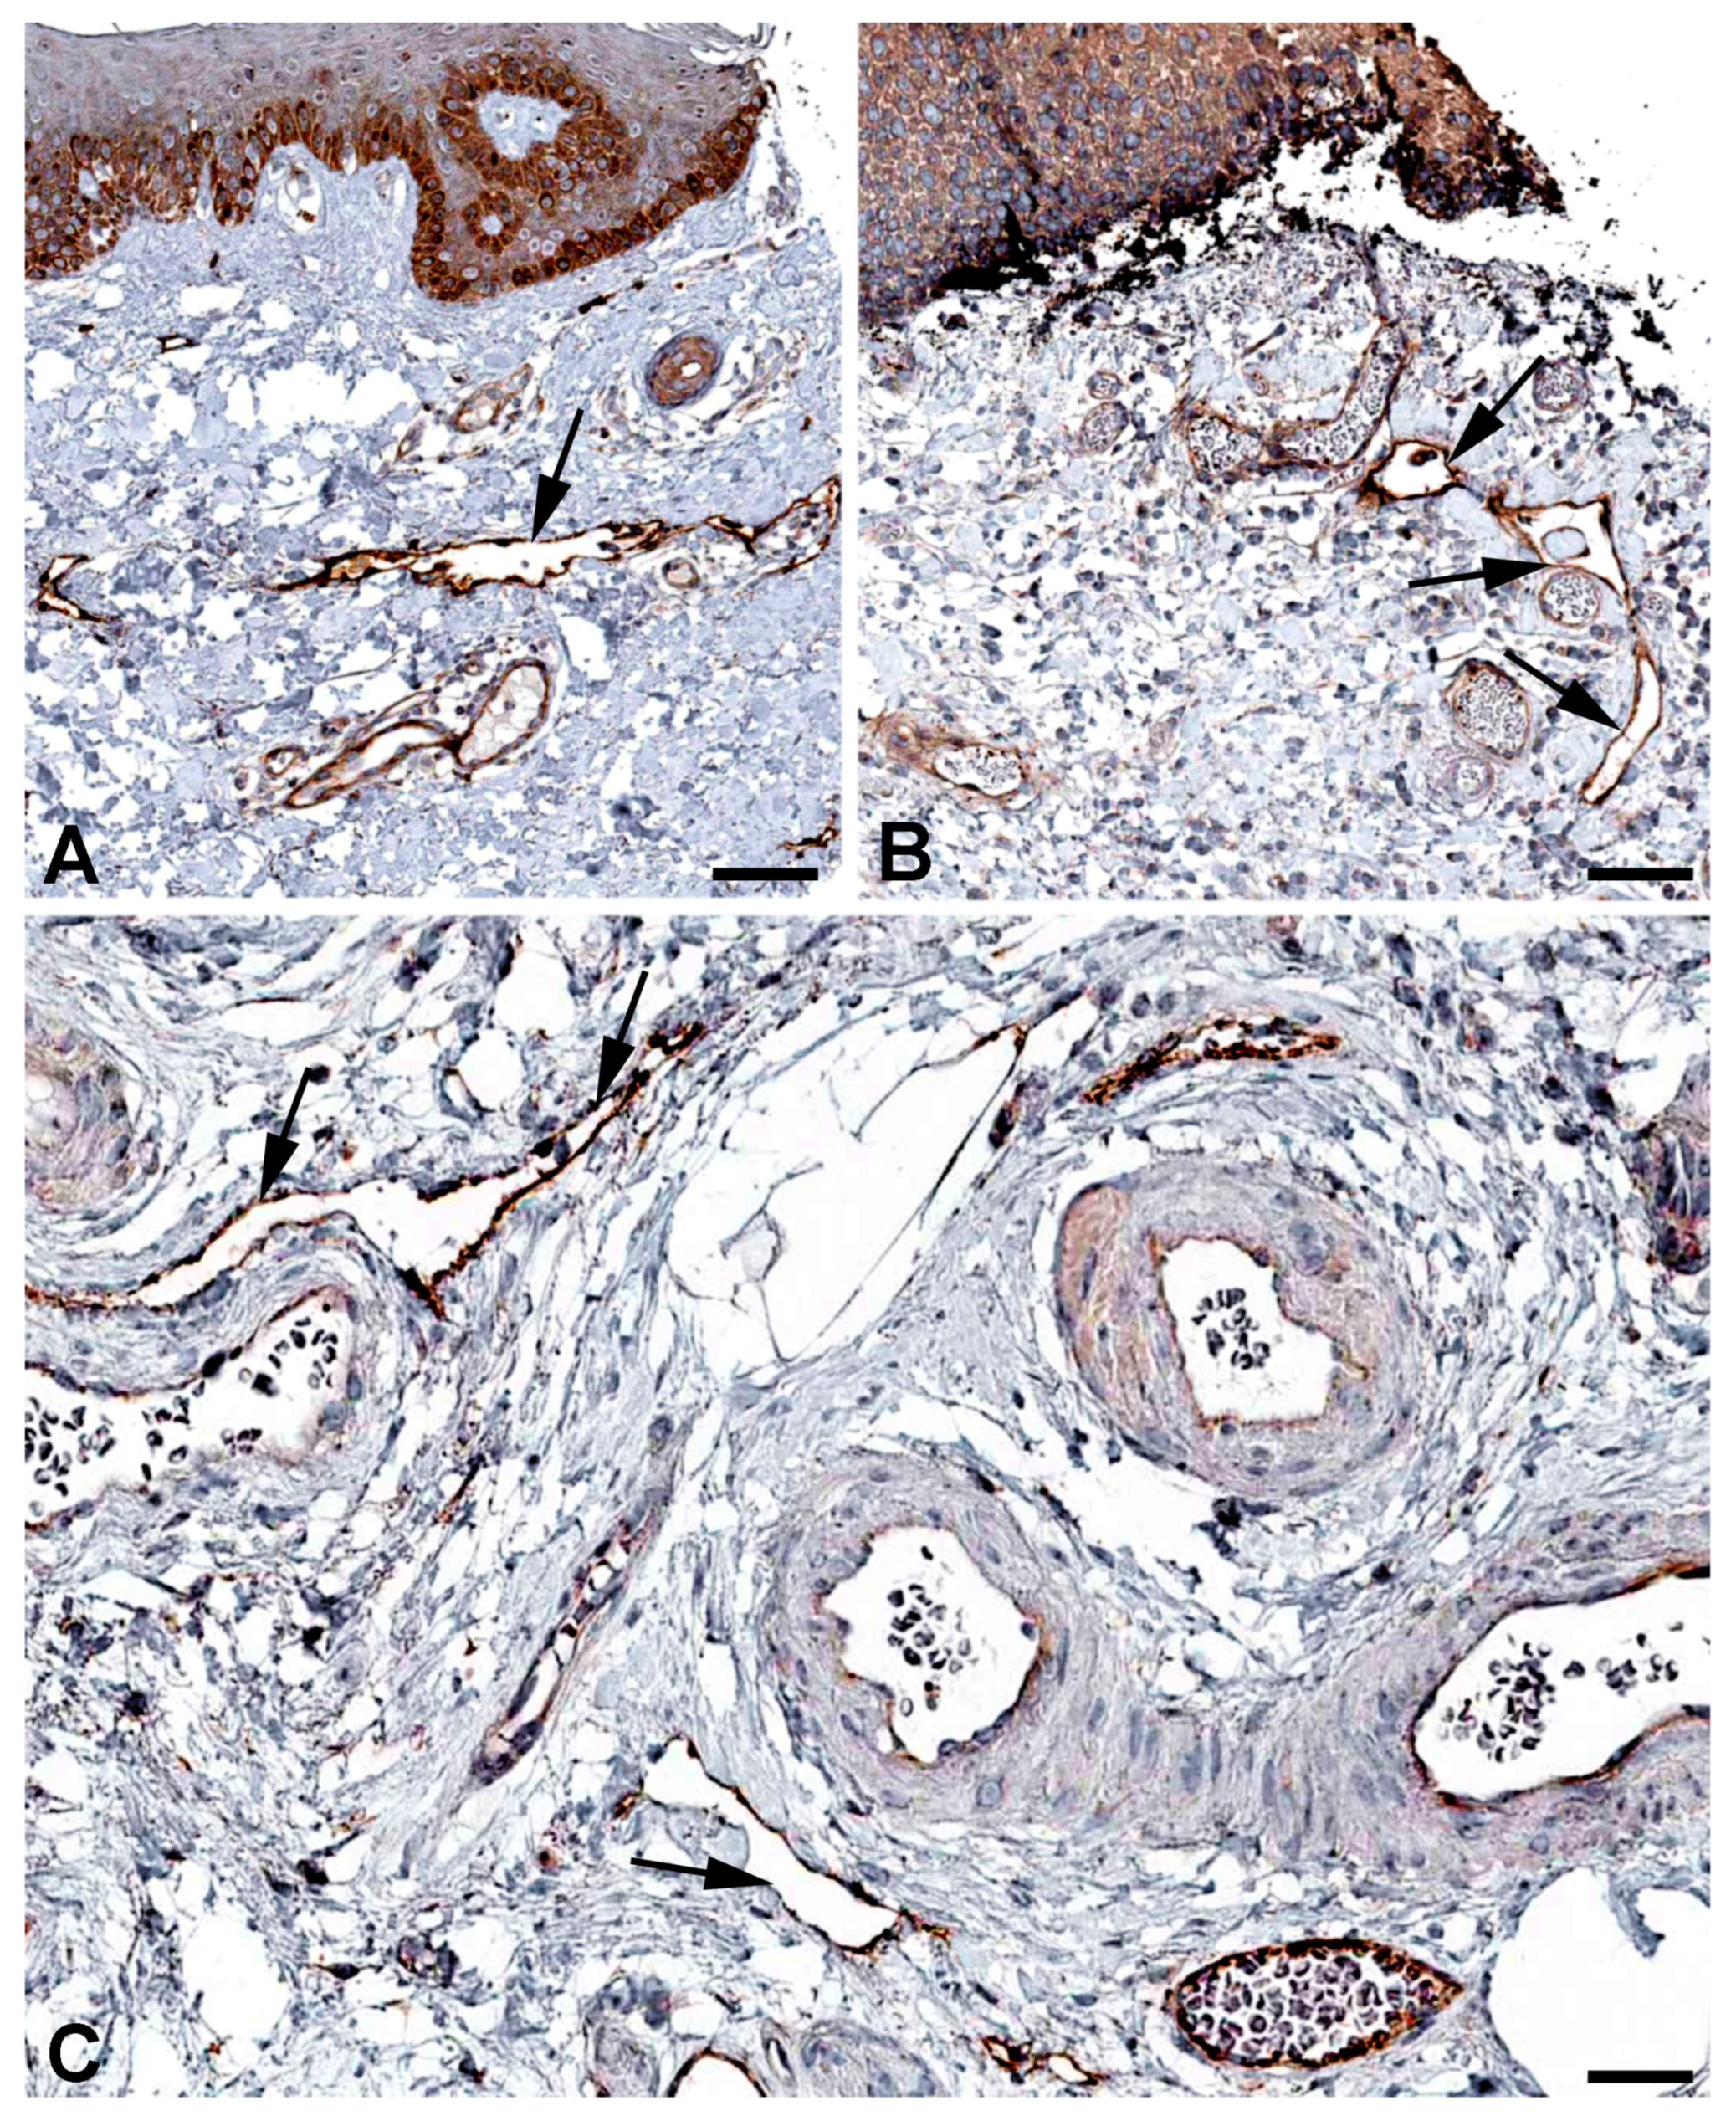

- Hasselhof, V.; Sperling, A.; Buttler, K.; Ströbel, P.; Becker, J.; Aung, T.; Felmerer, G.; Wilting, J. Morphological and Molecular Characterization of Human Dermal Lymphatic Collectors. PLoS ONE 2016, 11, e0164964. [Google Scholar] [CrossRef]